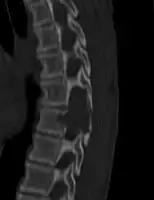

ABC in the spine may cause spinal cord compression.[1]

X-ray and CT scan show lytic expansion lesions with clear borders.[1] Expansion of cortex gives the lesion a balloon-like appearance. Larger lesions may appear septated.[10] MRI reveals fluid levels.[1] Bone scan shows outer radiotracer uptake, with a central dark area.[1]

CT scan: ABC spine -